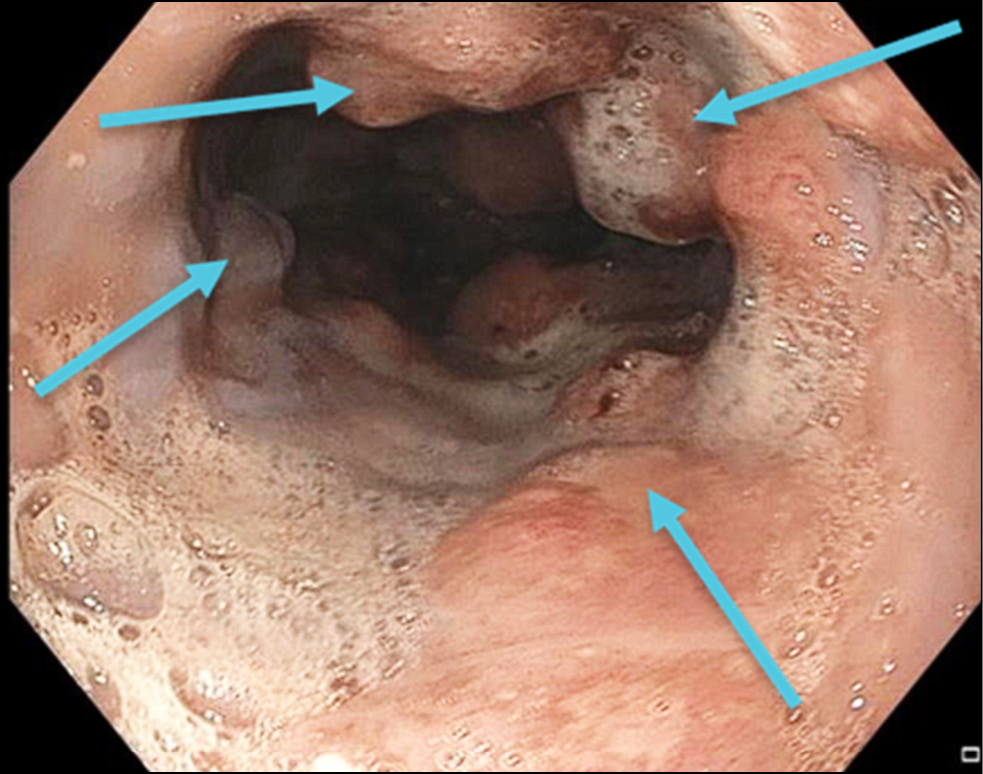

The patient was referred to a tertiary cancer center. Endoscopy at the cancer center showed the proximal edge of esophageal tumor infiltration at a site 24 cm from the incisors. The tumor appeared as multiple whitish-red merging lesions that spread circumferentially to the subcardial stomach. Deep ulcers covered with fibrin and necrotic plaque were observed. A fistula opening was found in the tumor tissue at a site 36 cm from the incisors, with the creamy opalescent contents flowing into the lumen. The esophageal lumen was significantly narrowed by the exophytic component of the tumor (Fig. 3). The tumor tissue was dough-like in texture and bled easily upon contact. The circumferentially infiltrated cardioesophageal junction was visualized at a site 44 cm from the incisors. The tumor infiltrated along the posterior wall to the subcardia (Fig. 4).

Fig. 3. Endophoto. Stenosing adenocarcinoma associated with Barrett`s esophagus. Blue arrows indicate areas of circularly located tumor.